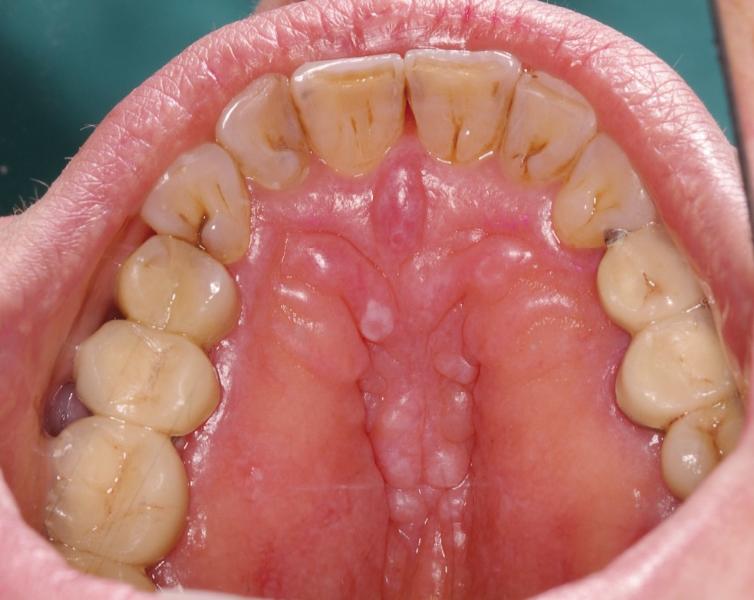

Fibromatosis gingival, (fibromatosis del paladar)